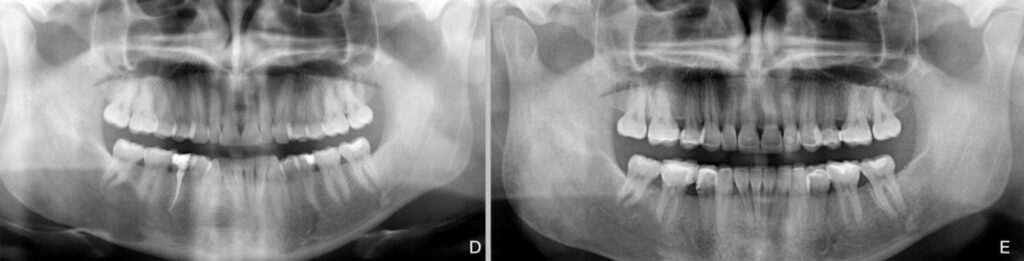

Figure 2. Patient 2. Generalized severe pathological tooth wear (TWES 2.0). (A) Pre-orthodontic intraoral

situation showing a class II, division 2 occlusal relationship accompanied by severe crowding

in the mandible. (B) Occlusion after orthodontic and restorative treatment, showing considerable

aesthetic and functional improvement. (C) A 5-year follow-up photograph to underline the maintenance

of occlusal contact relationships. Slight chronic gingivitis due to plaque accumulation can be

observed. (D) Initial orthopantomography. (E) Final orthopantomography showing supplementation

from 1.6 to 2.6 and from 3.6 to 4.6 by means of occlusal and vestibular lithium disilicate veneers.